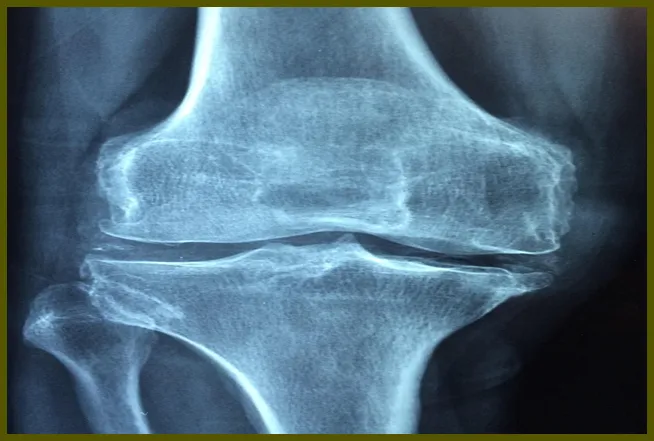

영상 검사와 의사의 소견

필요에 따라 X-ray, MRI 등의 영상 검사를 통해 관절의 상태를 평가하기도 합니다. 이러한 검사 결과는 관절의 손상 정도를 가늠하는 데 중요한 정보를 제공합니다. 의사는 환자의 임상 증상과 검사 결과를 종합적으로 고려하여 진단을 내리게 됩니다.